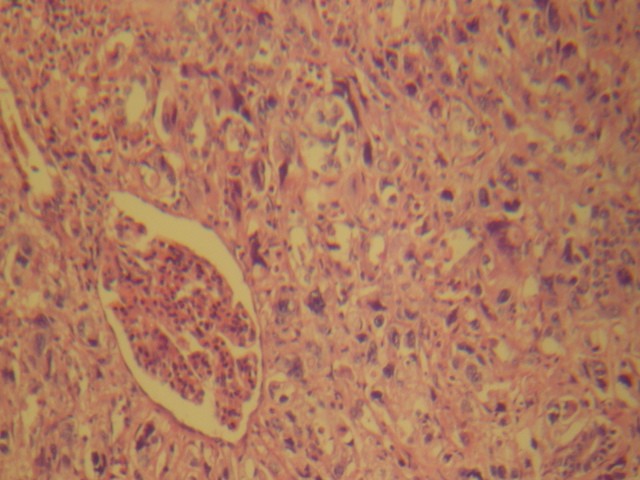

- <div style=fiogf49gjkf0dFoto 10- Origen del carcinoma en grandes conductos pancreáticos, presencia de gran conducto con metaplasia y displasia de su epitelio y conducto mediano en esquina superior izquierda revestido por células francamente neoplásicas. Pequeño acúmulo de esosinófilos">

fiogf49gjkf0d

Foto 10- Origen del carcinoma en grandes conductos pancreáticos, presencia de gran conducto con metaplasia y displasia de su epitelio y conducto mediano en esquina superior izquierda revestido por células francamente neoplásicas. Pequeño acúmulo de esosinófilos